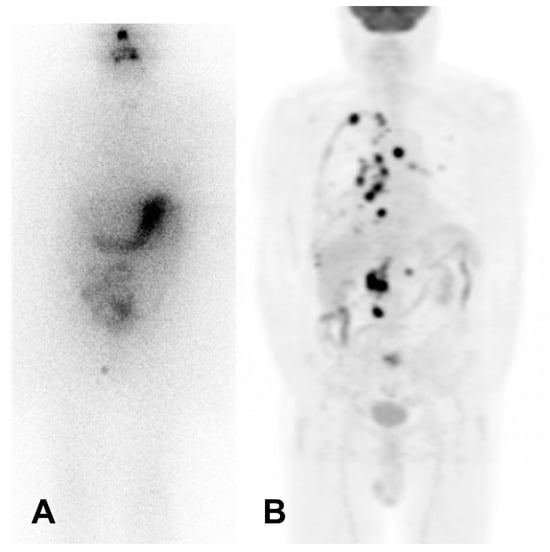

Figure 1. Patient with negative post-treatment whole-body radioiodine scintigraphy (A) and multiple [18F]FDG-avid lesions (B). Legend: male, 67 years, affected by papillary thyroid carcinoma with increasing thyroglobulin level 2 years after thyroidectomy and radioiodine therapy [4.4 GBq]. (A) Post-treatment whole-body scintigraphy [7.4 GBq] showing no radioiodine-avid lesions. (B) [18F]FDG PET/CT: multiple [18F]FDG-avid lesions in the mediastinum and lung, with an associated [18F]FDG-active pleural effusion (right side), and [18F]FDG-avid lesions in the retroperitoneal region. A biopsy on an abdominal lesion confirmed metastasis of papillary thyroid carcinoma.